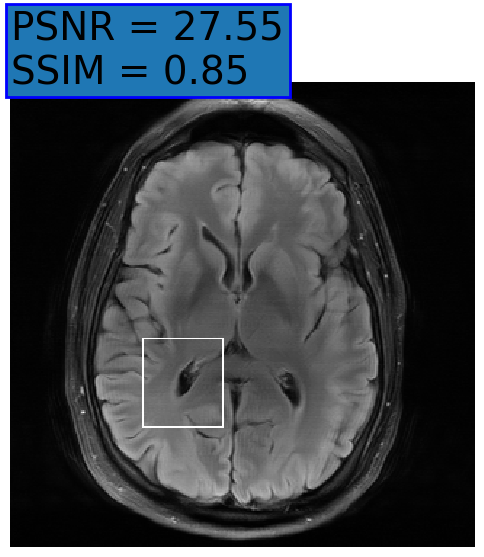

Figure 3: Examples of Reconstruction Results. Rows 1 and 3: The Ground truth (GT) fully sampled image, the reconstructed images obtained by the three models (1-3), NPB-REC, baseline, E2E-VarNet trained with Dropout, and the Std. map derived from our method for acceleration rates R=4𝑅4R=4, R=8𝑅8R=8, respectively. Rows 2 and 4: The corresponding annotated ROIS of the edema and resection cavity.

Fig. 3 presents examples of reconstruction results obtained by (1) our NPB-REC approach, (2) the baseline, and (3) Monte Carlo Dropout, for equispaced masks with two different acceleration rates R=4𝑅4R=4 and R=8𝑅8R=8. Table 1 presents the mean PSNR and SSIM metrics, calculated over the whole inference set, for the three models. our NPB-REC approach achieved significant improvements over the other methods in terms of PSNR and SSIM (Wilcoxon signed-rank test, pmuch-less-than\ll1e-4). The improvement in the reconstruction performance can be noted both quantitatively from the metrics especially for masks with acceleration rate R=8𝑅8R=8 and qualitatively via the images of annotations, where our results shows less smoothness than that obtained by Dropout.